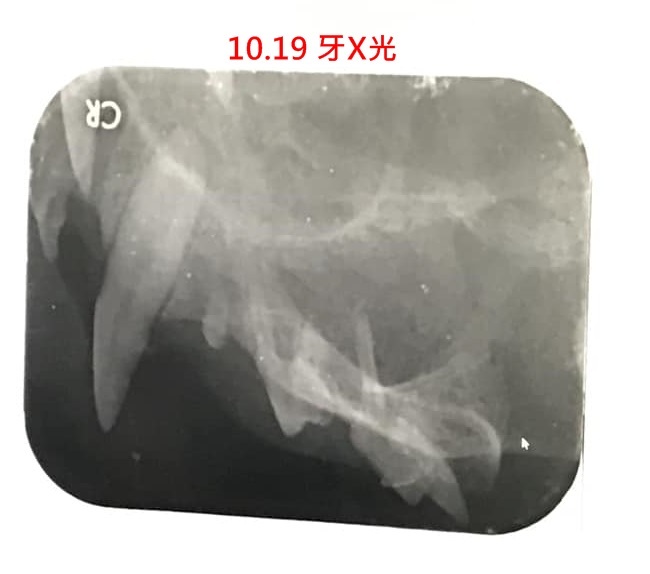

破牙細胞在乳牙替換成永久齒的過程中是正常細胞,但在成年貓咪身上保持活躍,就會對牙根造成破壞,診斷須要由牙科X光查看牙根骨槽,於是在10月19日進行X光檢查並同時治療,經X光檢查,可夢有貓破牙細胞及牙周病,於是依口腔狀況,拔除了十餘顆牙齒、留前犬齒及門牙,術後回診二次,恢復情況良好。本筆醫助為可夢在維康醫院的看診及牙周手術費用,希望大家可以幫忙,非常感恩。

內湖維康 可夢照齒科X光&拔牙

可夢牙齦紅腫、牙根外露,

除有牙周病、破牙細胞吸收症,

依口腔狀況,拔除十餘顆牙齒、留前犬齒及門牙。

日後視狀況治療,需定期回診。